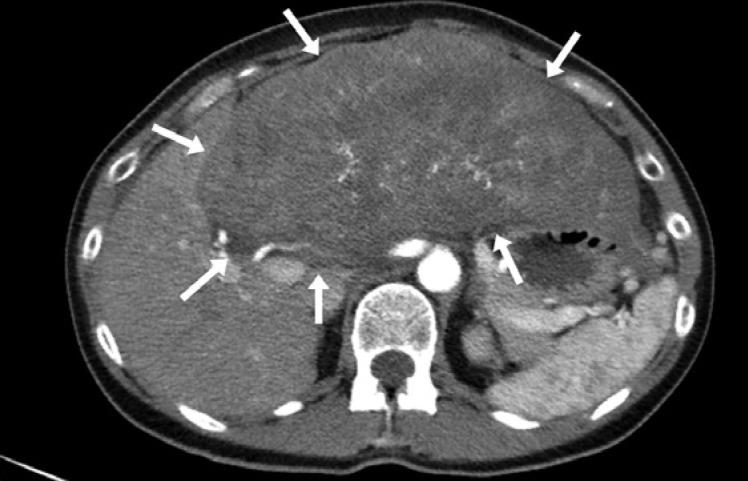

Combined hepatocellular-cholangiocarcinoma (CHC) is a rare type of primary liver cancer, speculated to arise from hepatic progenitor cells, and with a worse prognosis than hepatocellular carcinoma (HCC). Serum alpha-fetoprotein (AFP) levels may be one prognostic factor. It has been suggested that checkpoint inhibition might be useful in the treatment of HCC where there is an increased expression of PD-1 and PD-L1 in the microenvironment. Its effect on CHC is unknown. We report a case with a large CHC, which was radically resected, but the 53-year-old female patient subsequently developed pulmonary metastases. Histology demonstrated low-differentiated CHC without microsatellite instability. Treatment with sorafenib was started but was stopped due to angioedema. Under subsequent gemcitabine/cisplatin treatment, the metastatic disease progressed with rising AFP levels. A third-line treatment with pembrolizumab was then started, 2 mg/kg b.w. i.v. every third week for 6 months. This resulted in a radiologically complete remission of the pulmonary metastases and AFP levels were normalized (<10 μg/L) from a level of 1,790 μg/L before treatment. The patient developed immune-related adverse events (AEs) including diarrhea and hepatitis. These AEs were successfully treated with prednisolone and mycophenolate mofetil, and they were eventually resolved. There are no signs of cancer recurrence neither in the liver nor in the lungs at 33 months after the start of the checkpoint inhibition treatment, and the patient is doing well. Further study is urgently needed on the role of checkpoint inhibition therapy in liver cancer.

肝细胞-胆管细胞癌(CHC)是一种罕见的原发性肝癌,推测起源于肝祖细胞,预后比肝细胞癌(HCC)更差。血清甲胎蛋白(AFP)水平可能是一个预后因素。有人提出,在微环境中PD-1和PD-L1表达增加的HCC治疗中,检查点抑制可能有用。其对CHC的作用尚不清楚。我们报告一例大的CHC患者,该患者接受了根治性切除,但这位53岁的女性患者随后发生了肺转移。组织学显示低分化CHC,无微卫星不稳定性。开始使用索拉非尼治疗,但因血管性水肿而停药。在随后的吉西他滨/顺铂治疗下,转移性疾病进展,AFP水平升高。然后开始使用帕博利珠单抗进行三线治疗,静脉注射,体重2mg/kg,每三周一次,共6个月。这导致肺转移灶在影像学上完全缓解,AFP水平从治疗前的1790μg/L恢复正常(<10μg/L)。患者出现了包括腹泻和肝炎在内的免疫相关不良事件(AE)。这些AE通过泼尼松龙和霉酚酸酯成功治疗,最终得到缓解。在检查点抑制治疗开始33个月后,肝脏和肺部均无癌症复发迹象,患者情况良好。迫切需要进一步研究检查点抑制疗法在肝癌中的作用。